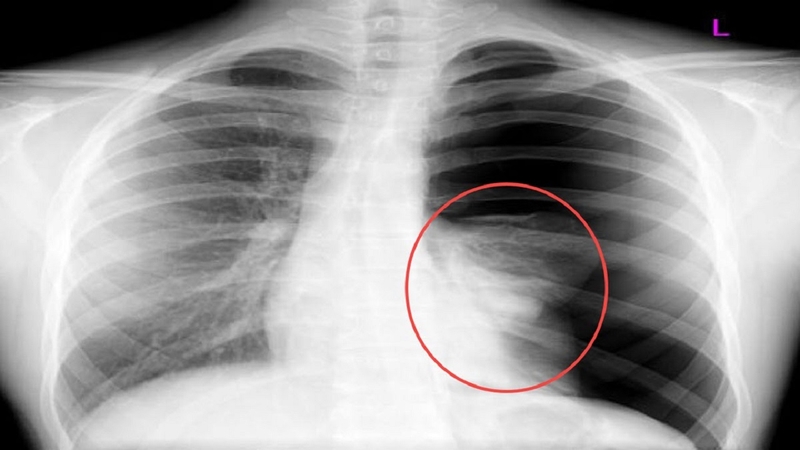

Triệu chứng viêm tiểu phế quản thường khởi phát với các biểu hiện giống cảm lạnh thông thường như sổ mũi, nghẹt mũi, ho khan và sốt nhẹ. Sau đó, trẻ sẽ xuất hiện các triệu chứng hô hấp rõ rệt hơn như ho nhiều, thở khò khè, thở nhanh và khó thở. Trong trường hợp nặng, trẻ có thể bị suy hô hấp, tím tái, cần được cấp cứu kịp thời. Việc chẩn đoán viêm tiểu phế quản thường dựa trên các triệu chứng lâm sàng và tiền sử bệnh. Bác sĩ cũng có thể chỉ định thêm một số xét nghiệm như xét nghiệm máu, chụp X-quang phổi để loại trừ các bệnh lý khác.